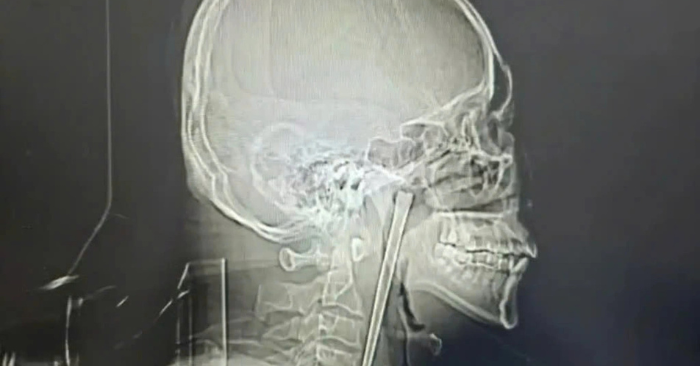

Kết quả chẩn đoán hình ảnh qua phim chụp X-quang xác định chính xác vị trí vật thể đang nằm tại vùng vòm miệng mềm của bệnh nhân. Các bác sĩ ghi nhận một sự may mắn lớn khi lớp niêm mạc xung quanh chưa bị tổn thương nghiêm trọng, các cơ quan lân cận không bị di lệch và đặc biệt là chức năng của dây thanh quản vẫn hoạt động ổn định.

Do bệnh nhân vẫn giữ quan điểm không đồng ý phẫu thuật rạch cổ như đề xuất cũ, các chuyên gia y tế đã quyết định sử dụng phương pháp can thiệp xâm lấn tối thiểu qua đường miệng. Ca phẫu thuật diễn ra thuận lợi theo đúng dự tính, dị vật dài 12cm được lấy ra hoàn toàn mà không gây mất nhiều máu hay để lại các biến chứng phức tạp cho sức khỏe.